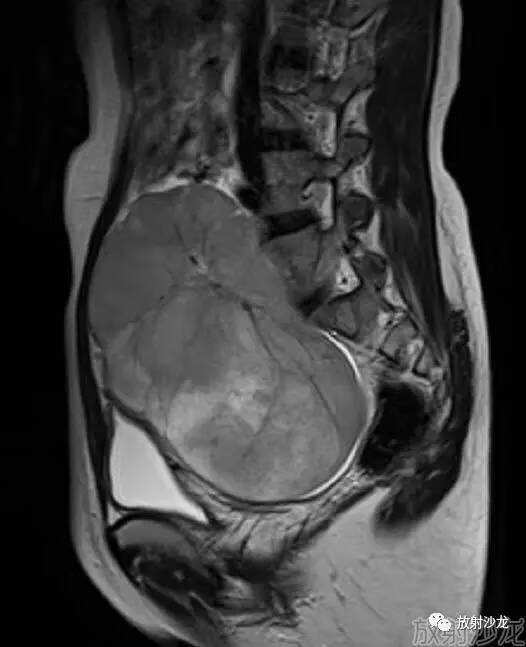

女性,26岁,发现盆腔肿块3个月,B超示盆腔实性占位。

@影像人:年轻女性,右侧附件区实质性为主肿块,病灶内可见多发短T2信号纤维分隔,应该先考虑胚生殖细胞源性肿瘤,无性细胞瘤可能

右侧卵巢无性细胞瘤

分叶状实质性肿块内纤维组织分隔和包膜,瘤内有出血或坏死及斑点状钙化

本例病变首先定位,冠状可以清晰显示左侧卵巢,来源右侧卵巢,实性肿块,DWI明显高信号,ADC值减低,恶性肿瘤,年轻女性恶性肿瘤生殖来源最常见,本病例特征表现多发纤维分隔,诊断应该考虑,来源右侧卵巢生殖系统恶性肿瘤,无性细胞瘤可能性大,您猜对了吗?